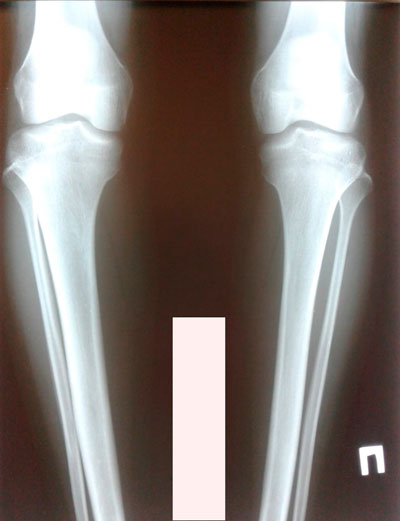

Исходник - 17 лет.

Дата операции - 25.06.2019.

Рентген в 70 дней.